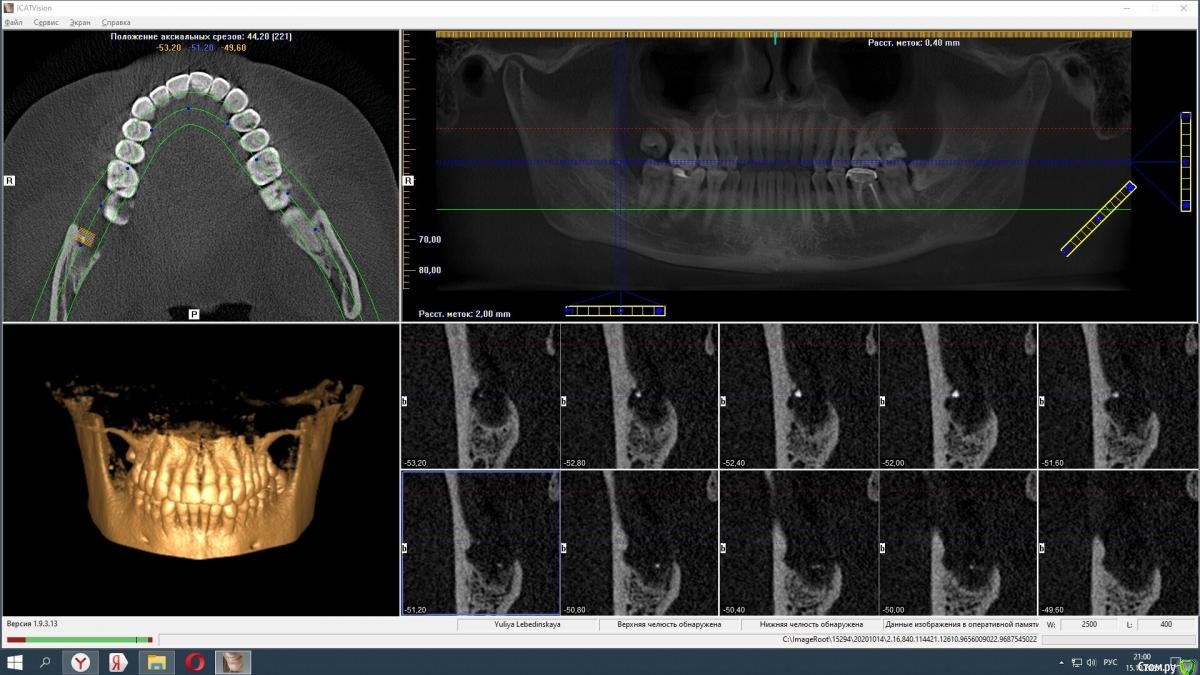

Спилка Опубликовано 15 октября, 2020 Поделиться Опубликовано 15 октября, 2020 В августе решилась на удаление нижних зубов мудрости (38 и 48). Врач - стоматолог-хирург посоветовала не удалять сразу оба, а по-очереди и начать с 48 зуба, ретинированного, дистопированного, возле которого больший очаг воспаления.В процессе удаления был сделан укол анестезии, потом разрезана десна, отпилена коронка зуба, упиравшаяся в соседнюю “семерку” - 47 зуб, и удалён корень, далее рана была зашита. В день операции прицельных снимков ни до, ни после не делали, врач руководствовалась КТ месячной давности, лунка после удаления не промывалась, лекарство, дренаж не ставились.Процесс удаления зуба прошел, на мой взгляд, быстро, дёргано, врач сразу же ушла после завершения, была не в настроении, явно чем-то обеспокоена. На свой счет я это не приняла, но осадок остался.Назначения врача в плане приема таблеток: нимесил, супрастин, амоксиклав, холод первые суткиАнтибиотик, в отличие от прочих назначений, был рекомендован при наличии болей на третий день после удаления.Меня предупредили, что операция сложная, “помучаюсь” с заживлением и восстановлением.Дома первые сутки прикладывала холод, пила нимесил и супрастин по нормам назначения.На третьи сутки супруг заметил, что изо рта стало “плохо пахнуть”, “гнилостно”, позвонил врачу, она сказала, что на третий день отёк самый большой, это норма, и посоветовала начать пить антибиотик, и если будет так же или лучше, все ок, если хуже - приехать на приём, лунку вскроют, заново сформируют сгусток и зашьют.На четвертые сутки после удаления ситуация ухудшилась, было принято решение показаться в областную клинику хирургу. В приемном отделении, увидев мою щеку, погоняли по кабинетам, взяли анализы, сделали рентген, КТ, ЭКГ, еще что-то - уже не помню, и …..поставили диагноз - флегмона околочелюстной области справа. И экстренно прооперировали. Подробности описывать не буду, жутко все это, никому не пожелаю... 11 дней в стационаре, выписали с открытой раной на амбулаторное лечение к хирургу по месту жительства.Я всю жизнь по стоматологам, много разных сменила, читаю информацию, что-то понимаю, но все же я не специалист. Эта клиника самая лучшая и дорогая в области, думала уж там все будет отлично. Но пока лечилась в областном стационаре, много читала и возникли сомнения, что удаление произведено отлично.После того, как рана затянулась, попытались прояснить этот вопрос с клиникой, где удаляли зуб. Там сказали, что я не добросовестный пациент, что никаких установленных нормативов, протоколов лечения не существует, соответственно, врач ничего не мог нарушить при проведении операции по удалению 48 зуба, попугали стоимостью экспертизы. И вообще, после вмешательства врачей областной клиники уже доказать ничего нельзя, засомневались в верности диагноза - флегмона околочелюстной области справа. По мнению директора клиники и глав врача удаление проведено идеально - они смотрели записи камеры наблюдения.Собственно - вопрос в чем - может они правы и удаление действительно прошло “идеально” - как они утверждают, и флегмоны не было.У меня есть 3Д снимки за месяц до удаления и через полтора месяца после. Как могла в программе выставила диапазоны, сделала снимки экрана. И кажется мне, что там осколки зуба в лунке… Муж сделал фото лунки - по-моему осколок видно.Я в растерянности, если клиника отработала идеально, почему такие катастрофические последствия?!! Если так можно - оцените ситуацию в целом, так как теряюсь сформулировать какой-то конкретный вопрос. Заранее спасибо всем! Ссылка на комментарий

Спилка Опубликовано 15 октября, 2020 Автор Поделиться Опубликовано 15 октября, 2020 Загрузите кт на файлообменникhttps://yadi.sk/d/cU-dxQlKtbsNfQКЛКТ И фото места где был зуб Ссылка на комментарий

Irouil Опубликовано 16 октября, 2020 Поделиться Опубликовано 16 октября, 2020 Вот именно мнение клиницистов меня и интересует, насколько правильно меня лечилиИменно это сказать клиницист не может в принципе, такие заключения даются на экспертизе врачом-экспертомКакой результат по вашему достигнут в стационаре, не подохла?Я бы выразился иначе, но суть Вы передали верно: главная цель лечения пациентов в экстренной медицине (а инфекционные воспалительные процессы, в первую очередь флегмоны, в челюстно-лицевой области являются показанием именно для применения такого вида лечения) - спасение жизни, ибо угроза для нее была. Теперь по существу Во-первых я не вижу на предоставленной компьютерной томограмме потенциально инфицированных фрагментов, угрожающих Вашему здоровью. И расскажите подробнее про губу - отмечается ее онемение? Сможете обрисовать карандашом область онемения и сделать фото? Ссылка на комментарий

Zlata-doctor Опубликовано 17 октября, 2020 Поделиться Опубликовано 17 октября, 2020 (изменено) Я не вижу никаких осколков на представленных снимках. Замечу, даже если бы они там и были, это не может являться причиной флегмоны. Патофизиология данного процесса гораздо более сложна и связана также с особенностями флоры вашей полости рта, вашего иммунитета, с непростой анатомией данной области, сложностью удаления и другими факторами. И таки да, околочелюстной области как анатомического образования, не существует. Промывание, введение лексредств и дренирование проводятся врачом по показаниям, он не должен 100% это сделать, а иногда это и нежелательно. Также хочу Вам сказать, что здесь собрались врачи, которые абсолютно бесплатно в рамках своей компетенции пытаются помогать вам, пациентам. И никакая это не цеховая солидарность, просто проводить экспертизу и ставить вердикт на расстоянии, не имея полной задокументированной истории вашей болезни-непрофессионально, преступно и аморально. К сожалению, люди сейчас воспитаны на скандальных ТВ роликах, где диагнозы обвинения, а заодно и приговор раздаются на раз-два. Здесь такого горлопанства в погоне за сенсацией не будет. Мы вам очень сочувствуем и желаем скорейшего выздоровления. Изменено 17 октября, 2020 пользователем Zlata-doctor 5 Ссылка на комментарий